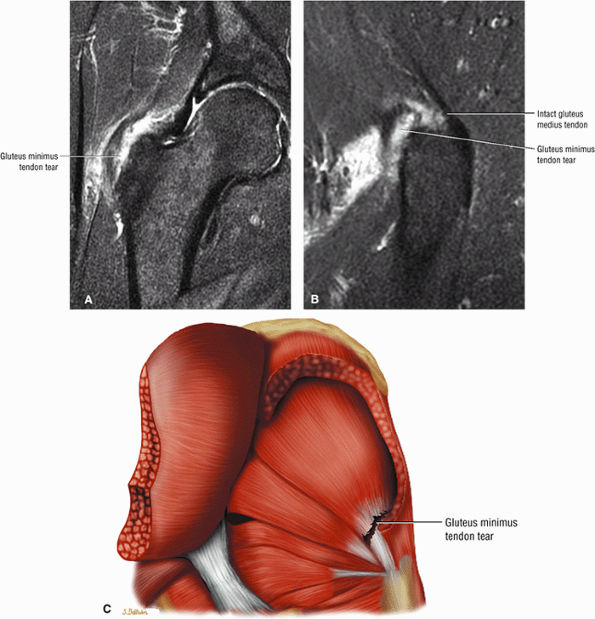

FIGURE 3.30 ● Normal sagittal anatomy of the hip. (A and B) On medial sagittal images, the course of the obturator internus, piriformis, and the adductor muscles can be followed and analyzed for strain injury or tears. (C and D) Tendinosis and tears of the common hamstring tendon origin on the ischial tuberosity are optimally viewed at this location and are extremely common in middle aged and elderly patients. (E and F) Although thinning and fraying of the articular cartilage can occur anywhere in the joint, chondral degeneration is most commonly seen first in the anterior superior quadrant, often accompanied by anterior labral tears, subchondral edema, and cystic change in the anterior acetabulum. When any one of these findings is present, a careful search for the others should be performed. (G and H) Linear tears of the anterior labrum can be mimicked by fluid filling a normal recess between the anterior labrum and the anterior joint capsule. Imaging in the axial and coronal planes is used to distinguish between a true tear and the normal recess, since a tear is visualized and confirmed in the axial and coronal planes, whereas a recess is only seen prominently in the sagittal plane. (K and L) The gluteus medius and minimus tendons have been referred to as the “rotator cuff” of the hip. The gluteus medius tendon inserts posteriorly on the greater trochanter, and the gluteus minimus tendon inserts anterolaterally on the greater trochanter. (I and J) Loose bodies commonly lodge in the joint recesses anterior and posterior to the femoral neck (deep to the iliofemoral and ischiofemoral ligaments). They are commonly seen (particularly in the sagittal plane) in patients with chondral degeneration. (M and N) Acute tears of the gluteus medius and minimus often mimic symptoms of a proximal femoral fracture. Chronic partial tears and tendinosis are frequently associated with trochanteric bursitis, and are common in middle-aged and elderly patients.